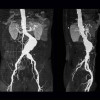

Etiologi Aneurisma Aorta

Proses degeneratif diduga merupakan etiologi utama pada aneurisma aorta. Penuaan menyebabkan perubahan pada kolagen dan elastin, sehingga mengurangi kekuatan dan elastisitas dinding aorta. Selain itu, aterosklerosis menyebabkan inflamasi pada dinding aorta dan memicu infiltrasi sel imun seperti limfosit dan makrofag.[1,2,5-8]

Faktor genetik juga diduga merupakan etiologi aneurisma aorta. Ada peningkatan risiko kejadian aneurisma aorta hingga 2 kali lipat pada orang dengan riwayat aneurisma aorta dalam keluarganya. Beberapa jenis RNA non-coding juga diekspresikan pada pasien aneurisma aorta, termasuk miR-21, miR-191-3p, miR-455-3p, dan miR-1281. Kondisi genetik tertentu yang menyebabkan gangguan jaringan ikat, misalnya sindrom Marfan dan sindrom Ehlers-Danlos, juga meningkatkan risiko aneurisma aorta.[1,2,5-8]